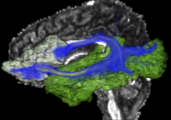

A new label map smoothing tool has been added to help with our collaboration with Children's Hospital Boston, SCI at University of Utah and Northeastern University. The unfiltered labelmap is shown in blue, and the filtered results are shown in peach.Image from Brad and Kilian on Wednesday, June, 21, 2007